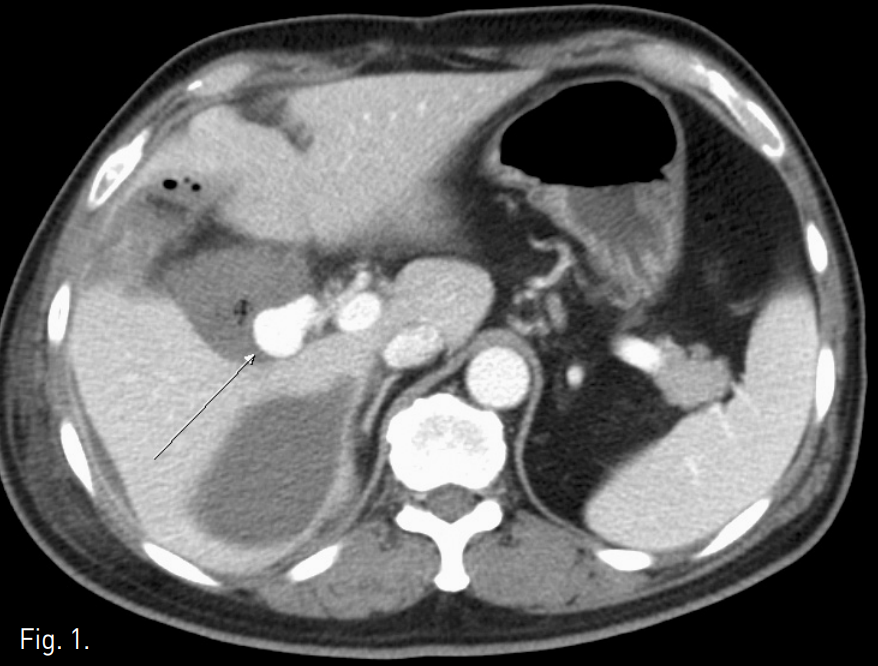

복부 컴퓨터단층촬영상 우측 간동맥 기원으로 생각되는 2.8cm 크기의 가성동맥류가 관찰되고 가성동맥류 주위에 complicated fluid collection과 air bubble들이 있으며, 간주위 공간과 오른쪽 가로막하 공간에도 complicated fluid collection이 있음(Fig. 1). 총간동맥 혈관조영술상 제 4 간분절(S4)로 가는 중간간동맥에서 기시하는 가성동맥류가 있으며 동맥류 안으로 조영제가 차 들어가는 것이 확인됨 (Fig. 2).

Fig. 1

Enhanced CT scan shows a 2.8-cm sized pseudoaneurysm (arrow) probably at the right hepatic artery and surrounding complicated fluid collection with multiple air bubbles. Another complicated fluid collection is seen in the perihepatic space